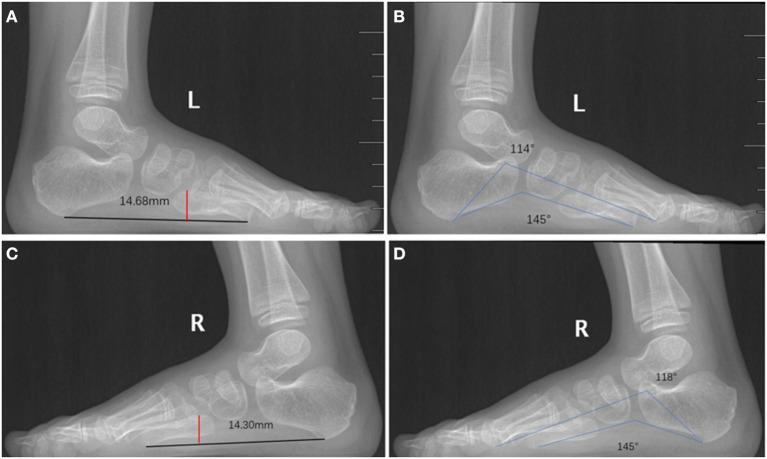

Polydactyly is a common deformity of the limbs, and excision of the extra digit has shown good results in the vast majority of patients. However, this treatment approach may not suitable for all cases of polydactyly. Some complex surgical procedures are required to treat rare forms of polydactyly and achieve satisfactory correction. Here, we report the use of on-top plasty technique for treating polydactyly between the 4th and 5th metatarsals with concomitant angulation of the 5th metatarsophalangeal joint. We performed the first osteotomy at the neck of metatarsal bone by "grafting" the distal polydactyly with the normal axis to the 5th metatarsal bone. Excision of the extra toe was accompanied by simultaneous restoration of the 5th toe axis and decrease in the width of the forefoot. Finally, both appearance and function could be improved. With this novel method, the complete osteoarticular structure and weight-bearing structure of foot were well-reconstructed. Based on the findings, we recommend that for the surgery of polydactyly, the beneficial parts should be preserved for reconstruction, and the tailored and personalized approach could be adopted.

多指畸形是一种常见的肢体畸形,绝大多数患者切除多余手指后效果良好。然而,这种治疗方法可能并不适用于所有多指畸形病例。治疗罕见类型的多指畸形并实现满意的矫正需要一些复杂的外科手术。在此,我们报告使用顶置成形术治疗第4和第5跖骨之间的多指畸形,并伴有第5跖趾关节成角。我们通过将具有正常轴线的远端多指“移植”到第5跖骨上,在跖骨颈部进行了第一次截骨术。切除多余脚趾的同时恢复了第5趾的轴线,并减小了前足的宽度。最终,外观和功能均得到改善。通过这种新方法,足部完整的骨关节结构和负重结构得到了良好重建。基于这些发现,我们建议对于多指畸形手术,应保留有益部分进行重建,并可采用量身定制的个性化方法。